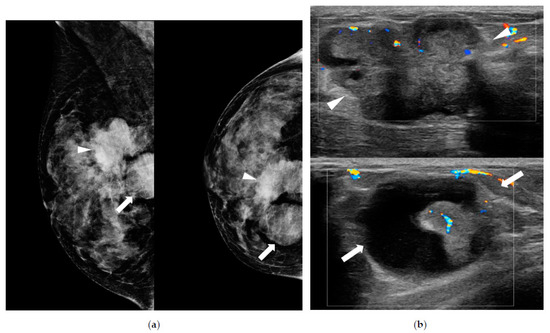

| Density on MG (n) Fatty Dense | 227 46 (15.30%) 181 (60.10%) | 136 16 (11.8%) 120 (88.2%) | 54 9 (16.7%) 45 (83.3%) | 37 21 (56.8%) 16 (43.2%) | <0.001 |

| Visibility on MG (n) (−) (+) | 227 129 (56.8%) 98 (43.2%) | 136 95 (69.9%) 41 (30.1%) | 54 29 (53.7%) 25 (46.3%) | 37 5 (13.5%) 32 (86.5%) | <0.001 |

| Type on MG Mass Asymmetrical Calcification only | 98 52 (53.0%) 38 (38.8%) 8 (8.2%) | 41 15 (36.6%) 23 (56.1%) 3 (7.3%) | 25 13 (52.0%) 8 (32.0%) 4 (16.0%) | 32 24 (75.0%) 7 (21.9%) 1 (3.1%) | 0.01 |